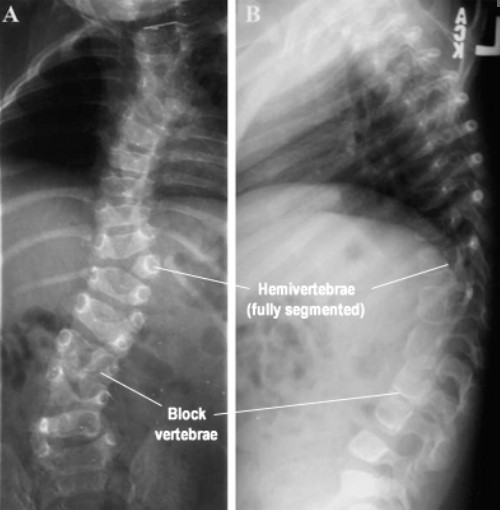

الجنف الخِلقي

ينتج الجنف الخِلقي عن تشوّهات في الفقرات تكون موجودة منذ الولادة، ويحدث نتيجة عدم اكتمال تطوّر العمود الفقري أثناء مرحلة النمو داخل الرحم.